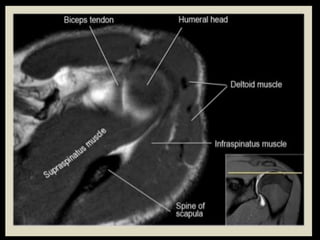

• 71.

• 85.

• 120.